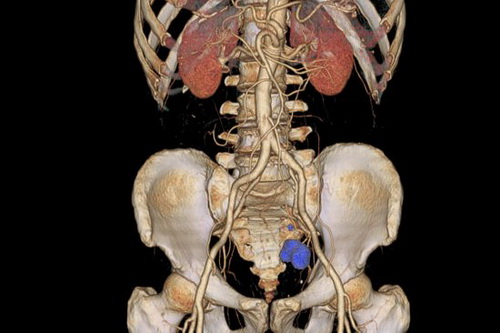

制作有用的医学图像涉及两个主要步骤:一是搜集数据,二是将这些数据转换为可快速、准确解读的图像。这张图像由一种称为X射线断层成像(简称CT)的先进X光技术生成,突出了上述两个方面的进步。体绘制软件(Volume-rendering software)结合CT血管成像技术,可以识别心脏附近主动脉(从图像顶端延伸至身体下部、心脏周围的大片粉色血管)的异常情况。再往下,可以清楚看到肝脏(紫色)和肾脏(鲜红色)。准确测定主动脉直径至关重要,因为外科医生可以借此判断主动脉是否存在破裂的风险。

在这张图中,PET扫描确认的癌组织是蔚蓝色圆团状物体,而CT扫描锁定了它在结肠的位置。

根据CT扫描,肾脏(红色)、骨骼和血管的结构也都清晰可见。PET技术最常用于肿瘤学检查,也应用于心脏病学和神经病学领域。生成此图的仪器制造商“GE Healthcare”日前引进了两种系统,帮助研究人员探索新的临床应用。据美国放射学学院的布鲁斯·希尔曼(Bruce Hillman)介绍,由于可以监测细胞功能,PET就是一系列用以监控人体细胞和亚细胞新工具的典型代表。